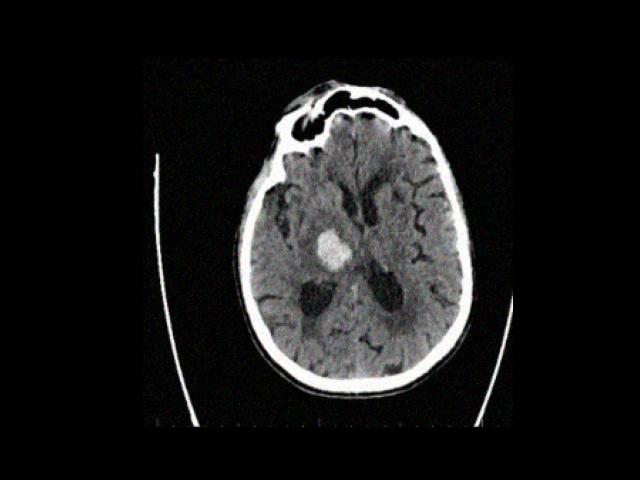

Sample Gallery